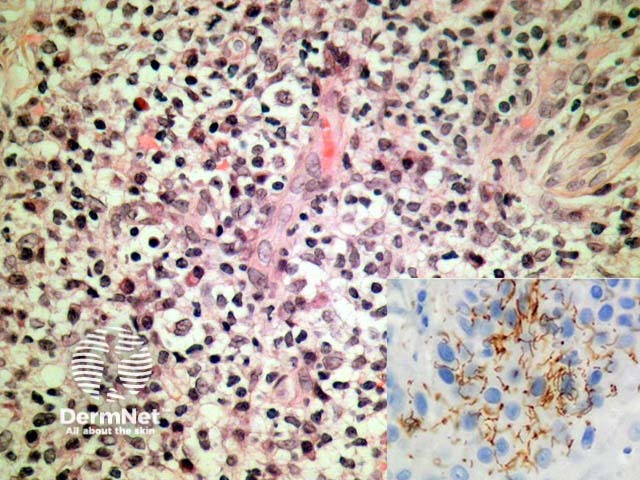

Primary syphilis (primary chancre) demonstrates an acanthotic epidermis which erodes with time to become ulcerated. Under the ulcer bed there is typically a dense lymphocytic response, numerous plasma cells, and endothelial swelling (figure 1). There are typically numerous organisms which may be exhibited with a variety of techniques including immunohistochemistry directed against Treponema pallidum (figure 1, inset).

Figure 1

Various special stains have been applied. The specific immunohistochemical stain for Treponema pallidum is highly specific and sensitive and reveal the organisms to be delicate and spiral shaped (figure 1, inset). Silver impregnation techniques such as Warthin Starry highlight the organisms. Dark-field examination, electron microscopy, and polymerase chain reaction (PCR)-based methods have also been used.